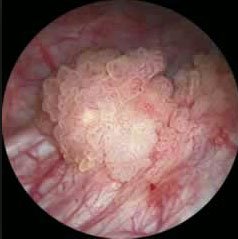

Mesane tümörü tanısı hastanın anamnezi, detaylı fizik muayene, radyolojik görüntüleme ve sistoskopi ile konulmaktadır. Radyolojik görüntüleme de ultrasonografi genellikle yeterli olmaktadır. Ancak bazen başlangıç aşamasında milimetrik boyutlu tümörler ultrasonografide atlanabilmektedir. Klinik şüphe halinde sistoskopi ( mesanenin kamera yardımıyla görüntülenmesi), ilaçlı bilgisaraylı tomografi, idrarda sitoloji bakılması, idrarda tümör markırları değerlendirilmesi (şu an için çok başarılı sonuçlara sahip değil) gerekebilmektedir. Yine ultrasonografik olarak tanı konulmuş olsa dahi tümörün mesane dışında doğru uzanımının ve olası uzak organ yayılımının (metastaz) değerlendirilmesi içinde bilgisayarlı tomografi(BT), magnetik rezonans görüntüleme(MR), pozitron emisyon tomografi (PET) gibi görüntüleme yöntemlerine ihtiyaç duyulabilir. Ancak mesane tümörü kesin tanısı sistoskopi ve eş zamanlı mesaneden biyopsi alınması ile konulur.

Şekil 3: Mesane tümörünün sistoskopik görüntüsü